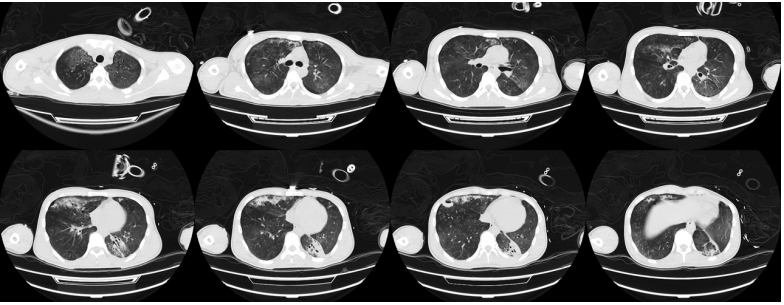

考虑到患者可能是病毒血症引起的全身非感染性炎症反应,于第7天决定选择甲泼尼龙(160 mg)给药1次,之后患者整体情况有所改善。密切监测其病原学,最终仅检出白色念珠菌,未在激素应用过程中出现曲霉感染。ECMO支持后(第8天)复查胸部CT可见双肺近乎完全实变,下肺尤为严重,肺内几乎没有有效通气(图4)。

图4 患者入院后胸部CT(第8天)

第2周:第8天再次予西多福韦治疗。应用甲泼尼龙160 mg后24 h内,患者循环逐渐稳定,去甲肾上腺素逐渐减量,氧合也有所改善。第11天在患者病情似乎好转情况下,发现出现气压伤,这可能与患者肺部渗出很快吸收,顺应性改善,但仍给予较高PEEP有关。此后快速调节呼吸机参数,逐渐下调ECMO。第11天患者血NGS回报腺病毒14型(序列数969)。第16天血NGS回报腺病毒14型(序列数6),提示患者病毒血症明显好转。

第3周:第16天复查胸部CT:患者病变在逐渐吸收,病情较前好转(图5)。撤离ECMO,患者进入康复阶段。期间患者在气管镜下出现气道内右上叶出血。为了避免出血加重,整体调整了抗感染及抗凝治疗,并予西多福韦治疗。复查BALF腺病毒核酸仍为阳性,但患者整体状况、呼吸功能及肺部病变情况在逐渐改善。

图5 患者入院后胸部CT(第16天)

第23天复查胸部CT:肺内仍有少量气压伤表现以及小结节(图6)。第28天复查NGS发现,BALF中腺病毒序列数为22,血中腺病毒序列数为6。再予一次西多福韦。肾功能遗留少量损伤,仍在间断进行肾脏替代治疗治疗。第30天胸部CT可见病变较前明显吸收好转(图7)。

图6 患者入院后胸部CT(第23天)

图7 患者入院后胸部CT(第30天)